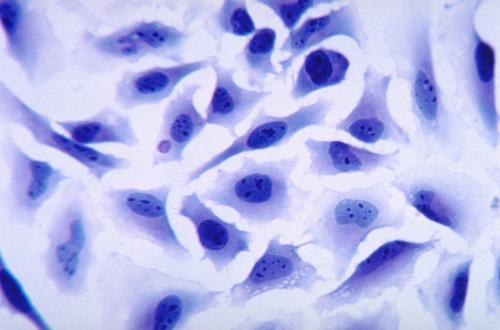

來源:藥渡撰文:四月的雨 編輯:丸子1概述許多藥物在體內(nèi)往往具有溶解度低、保留時間短、生物利用度低以及靶向能力較差等限制,而且大分子藥物如核酸和蛋白質(zhì),還很容易被各種酶快速降解,從而失去活性。基于細(xì)胞的給藥策略因其獨特的生物學(xué)特性,如優(yōu)良的生物相容性、低免疫原性、較長的循環(huán)時間以及跨越生物屏障的能力而備受關(guān)注。多種細(xì)胞可作為功能載體而用于藥物的遞送,如紅細(xì)胞、干細(xì)胞以及淋巴細(xì)胞等。由于這些細(xì)